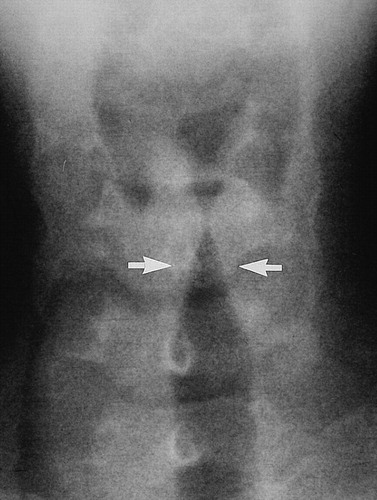

Chest X-ray